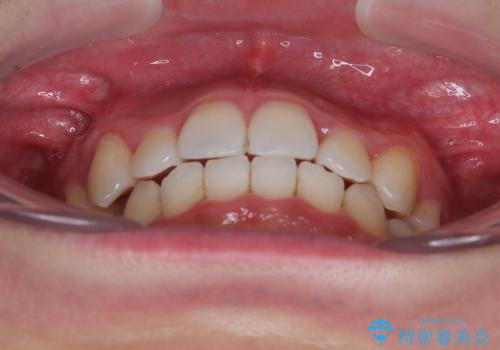

上下の八重歯とクロスバイト ワイヤー装置での抜歯矯正

- 八重歯とクロスバイトを気にして来院された患者様です。

上下ともに八重歯が顕著であり、前歯のクロスバイトがあったため、上下左右の第一小臼歯4本を抜歯し、ワイヤー装置での抜歯矯正を行うこととしました。